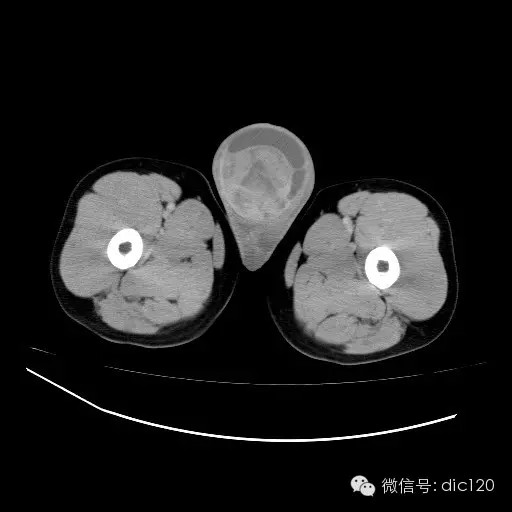

【影像表现】

青年男性,右侧睾丸肿大,边界清晰,增强后睾丸不均匀中度强化,内可见多灶囊变坏死区,动脉期肿块内有细小动脉血管显示,延迟期可见分隔样强化,鞘膜囊可见积液。

定位定性:右侧睾丸恶性肿瘤。

【影像诊断】

右侧睾丸精原细胞瘤,右侧睾丸鞘膜积液。